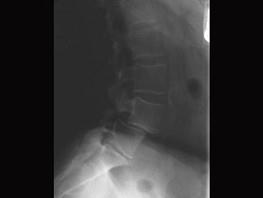

问题 关于腰椎滑脱下列哪项正确 ( )

选项 A、腰椎滑脱手术治疗最关键是滑脱复位与固定 B、腰椎正侧位X线片可清晰显示峡部情况 C、退变性腰椎滑脱常超过Ⅱ° D、峡部型滑脱多无明确的外伤史 E、腰椎滑脱均应积极手术治疗

答案 D